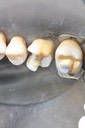

Larry Fujioka #29-30 pre-op

Larry Fujioka#29-30 amalgam removal

Larry Fujioka #29-30 prep

Larry Fujioka #30 buccal prep